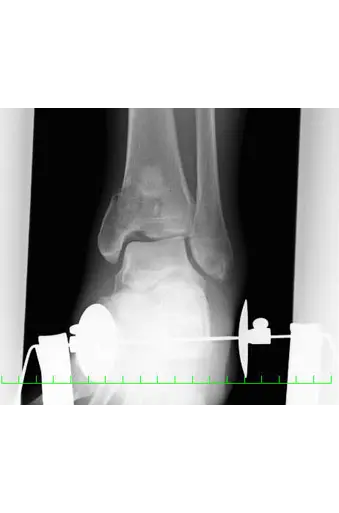

本症例は受傷直後に軟部組織の損傷を強く認め(足関節周囲は軟部組織が非常に薄い)、一期的なORIFは困難な状態であった。本症例のように軟部組織の損傷を強く認める状態でのORIFは感染、皮膚壊死といった問題が生じる危険性がある。そのため、軟部組織の回復まで一時的に鋼線牽引療法(traction)や創外固定術を施行し、軟部組織の炎症・腫脹が回復してきた後にORIF(two stage surgery)を施行する。

創外固定は、Ligamentotaxisにより骨折部や関節面の間接的整復と軟部組織の早期回復のためにtwo stage surgeryに頻用される。

Ligamentotaxis:伸延力(distraction forces)を加えることにより骨折部周囲の靱帯や筋肉に張力が働き、骨折部を間接的に整復することである。

関節内骨折の治療目標は、完全な関節面の再建と骨片間の圧迫により受傷前の状態に機能を戻すことである。そのためORIFを行うが、軟部腫脹が著しく早期にORIFを施行できない場合には創外固定術を施行する。本症例も腫脹が著しく、感染や皮膚壊死の危険があり創外固定術を行った。創外固定術は軟部組織保護のための一時的な処置で、通常1~2週間後に最終的なORIFを行い、本症例も創外固定術後14日目にORIFを施行した。